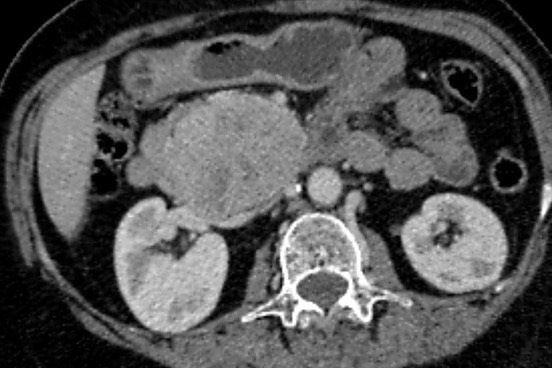

«Միքայելյան» համալսարանական հիվանդանոցում հերթական բարդ վիրահատությունն է իրականացվել, հեռացվել է ենթաստամոքսային գեղձի գլխիկի մեծ ուռուցք ավելի քան 10սմ տրամագծով, որը սերտ հպված էր միջընդերային զարկերակին և երակին:

Առհասարակ ենթաստամոքսային գեղձի գլխիկի մեծ չափի ուռուցքները համեմատաբար քիչ են հանդիպում: Առավել քիչ են հանդիպում այն դեպքերը, երբ գեղձի գլխիկի մեծ չափերի ուռուցքը չի առաջացնում մեխանիկական դեղնուկ: Համալսարանական հիվանդանոցի Վիրաբուժության կլինիկա է դիմել 62 տ. կին՝ գանգատվելով ցավից և ծանրության զգացումից վերորովայնային (էպիգաստրալ) շրջանում:

Կատարվել է պանկրեատոդուոդենալ մասնահատում, տեխնիկական դժվարություններով ուռուցքն անջատվել է վերին միջընդերային երակից և զարկերակից:

Հեռացված հյուսվածքի հետազոտությամբ հայտնաբերվել է ենթաստամոքսային գեղձի գլխիկի նեյրոէնդոկրին ուռուցք: